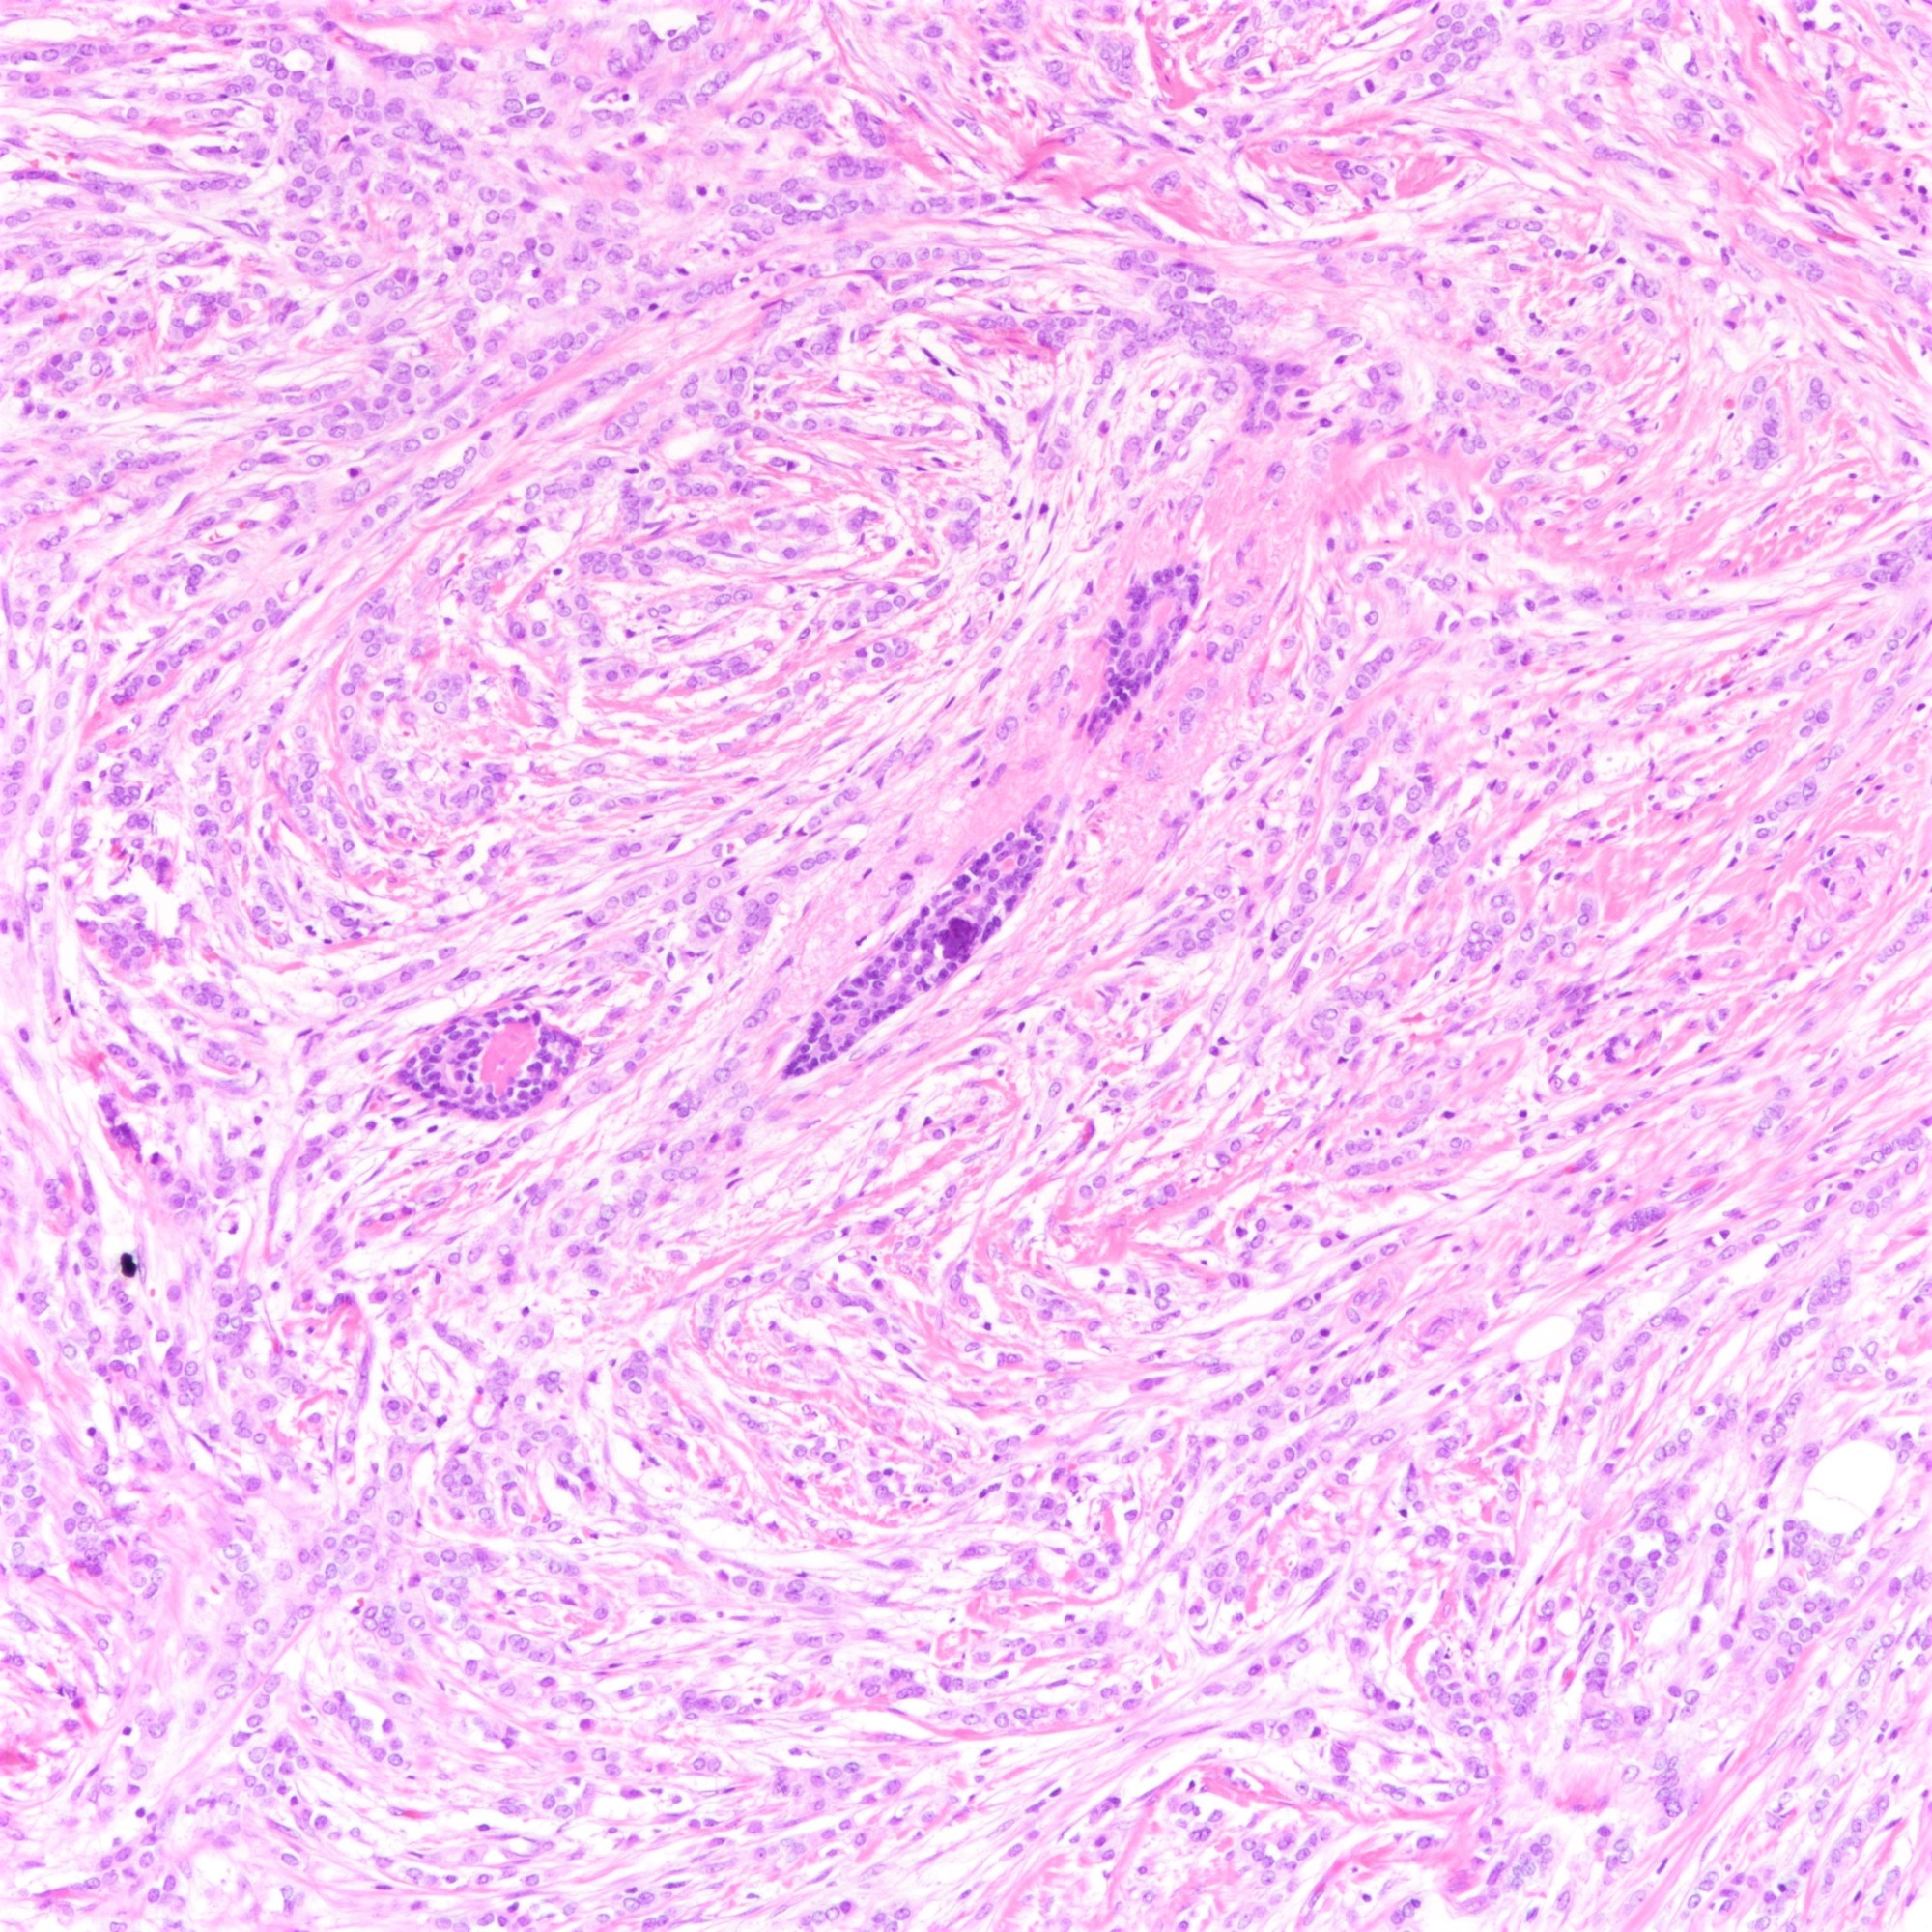

Microscopic (histologic) description

- Tumor cells arranged in single files, cords and single cells (Breast Cancer Res 2015;17:12)

- Can be arranged concentrically around normal ducts, giving a targetoid appearance

- Tumor cells discohesive, small, monomorphic and lacking marked atypia

- Round or notched ovoid nuclei, usually grade 1 or 2 nuclear score

- Scant cytoplasm, occasional with intracytoplasmic lumen

- Mitosis infrequent

- Desmoplastic reaction and necrosis uncommon

Microscopic (histologic) images